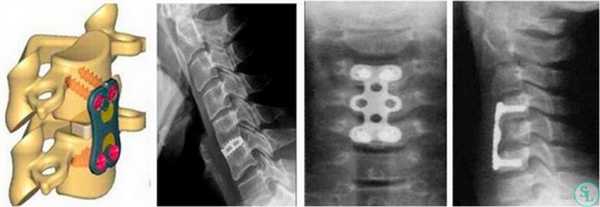

Межтеловой кейдж для фиксации позвонков

Чтобы операция дала наилучший результат, часто используется межтеловой кейдж, который должен отвечать таким требованиям:

- обеспечивать стабильность тел позвонков;

- гарантировать сохранение нормальной высоты межпозвоночных дисков, что позволяет избежать компрессии нервов;

- быть изготовленным со специальным пространством через которое, можно вводить костный цемент, искусственную костнозамещающую крошку или препаратов увеличивающих рост костной ткани ;

- Корригировать и фиксировать боковой (сагиттальный) и передний (фронтальный) баланс позвоночника;

- Удерживать нагрузку которая ложиться на ось позвоночника.

Безусловно, предельно качественное выполнение ТПФ обеспечивается при применении устройств 3-го поколения. Современные имплантируемые кейджи позволяют надежно зафиксировать патологически измененный сегмент позвоночника и устранить болевой синдром, обусловленный его остаточной подвижностью.